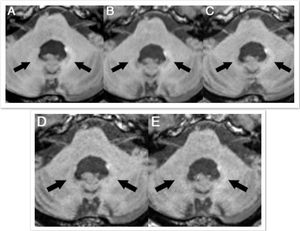

"Post-MRI signals disappear with macrocyclic gadolinium" Axial MR images of a patient before (A) and after nine (B), 17 (C), 29 (D), and 41 (E) administrations of gadobutrol and gadoterate meglumine. Pre-existing hyperintensities in the dentate nucleus (most likely related to prior linear GBCA injection) are visible in all images. There is a slight decrease in hyperintensities between the baseline MRI and the MRI after 41 injections of macrocyclic GBCAs. Images courtesy of Radiology.